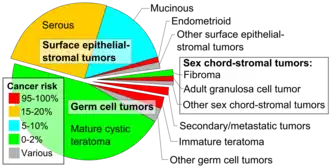

Surface epithelial-stromal tumor

Surface epithelial-stromal tumors are a class of ovarian neoplasms that may be benign or malignant. Neoplasms in this group are thought to be derived from the ovarian surface epithelium (modified peritoneum) or from ectopic endometrial or fallopian tube (tubal) tissue. Tumors of this type are also called ovarian adenocarcinoma.[1] This group of tumors accounts for 90% to 95% of all cases of ovarian cancer; however is mainly only found in postmenopausal women with the exception of the United States where 7% of cases occur in women under the age of 40.[2][3][4][5][6][7] Serum CA-125 is often elevated but is only 50% accurate so it is not a useful tumor marker to assess the progress of treatment. 75% of women with epithelial ovarian cancer are found within the advanced-stages; however younger patients are more likely to have better prognoses than older patients.[8][9][10][11][12]

Classification

Epithelial-stromal tumors are classified on the basis of the epithelial cell type, the relative amounts of epithelium and stroma, the presence of papillary processes, and the location of the epithelial elements. Microscopic pathological features determine whether a surface epithelial-stromal tumor is benign, a borderline tumor, or malignant (evidence of malignancy and stromal invasion). Borderline tumors are of uncertain malignant potential.

This group consists of serous, mucinous, endometrioid, clear cell, and brenner (transitional cell) tumors, though there are a few mixed, undifferentiated and unclassified types.